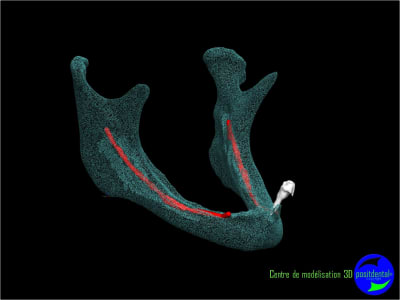

Il faut faire une ostéotomie en forme de tube au niveau de 33 et 43 et y placer deux tiges cylindro-coniques en titane. Quelques mois après tu pourras t'en servir pour fixer la prothèse.

Résorbée genre comme ça?

Sur une mandibule fortement résorbée la pose de 2 implants ne vont pas résoudre les douleurs occasionnées par la compression du nerf dentaire inférieur.